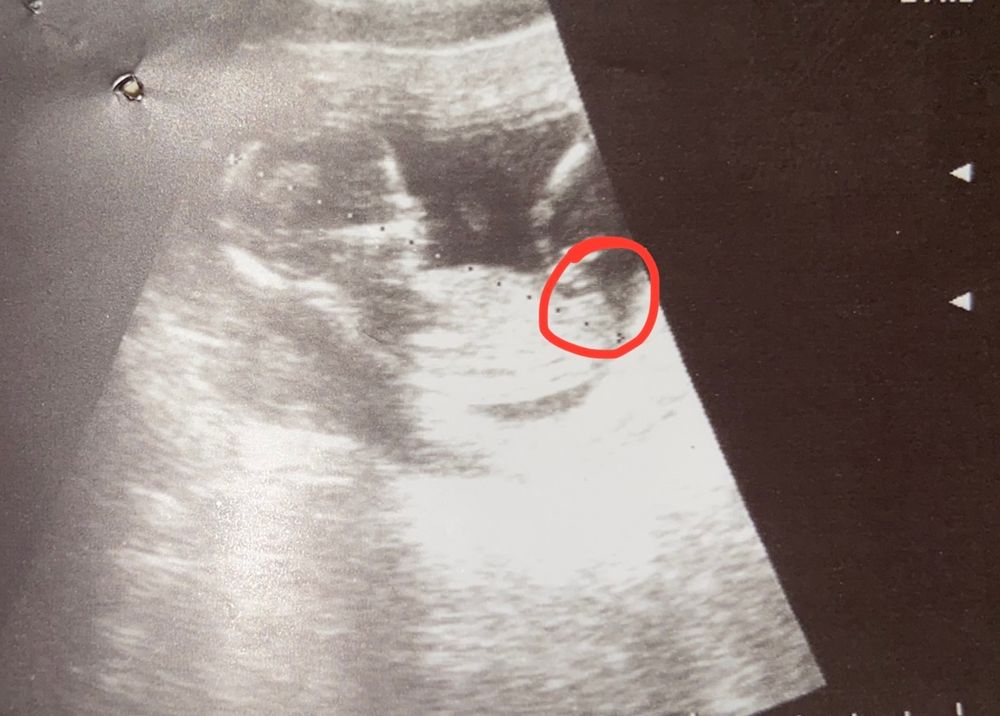

Нашла бугорок старшей девочки😆

Пока не подтвердят мне пол, по узи,не успокоюсь 😂 вот нашла узи старшей девочки(где красным обведен), бугорки под разным углом, что у нее, что сегодня делала узи, очень большая надежда, что мальчик🥺